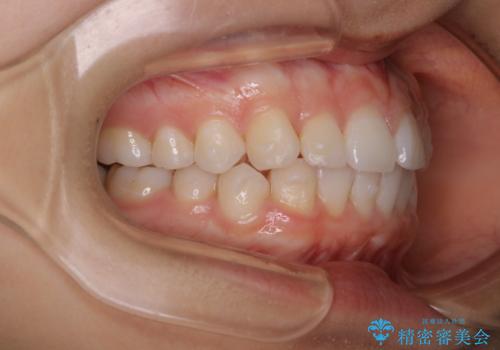

前歯のがたつきをインビザラインで治療

- 上下前歯のがたつきが気になるとの事で来院された患者様です。がたつきの程度が軽度であったため、インビザラインライトにて治療をおこないました。

がたつきの程度が軽度であったことと、インビザラインを正しく装着して頂けたことで短期間で治療終了することが出来ました。